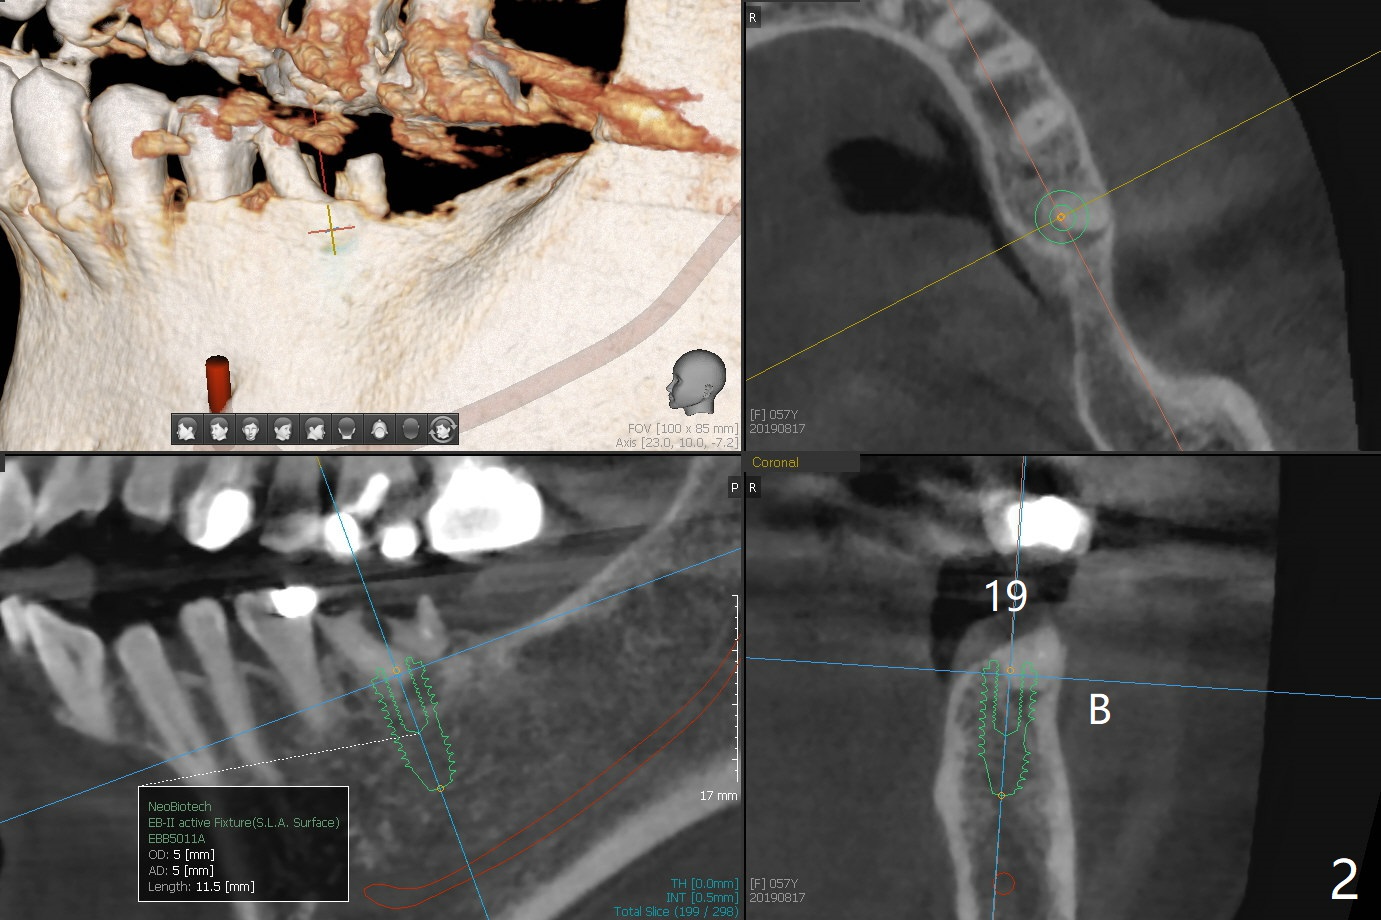

A 57-year-old woman agrees to have implants at #18 and 19 (Fig.1). Since the tooth #15 is supraerupted and there is limited vertical space at #18 (Fig.3), Magicore and FC will be placed at #18 and 19, respectively (Fig.3,2).